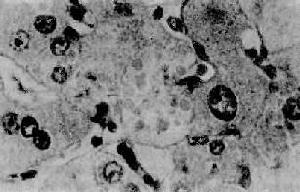

輕症酒精性肝病中可見酒精性肝病的基本病變,如大泡脂變、灶壯氣球樣變、壞死灶伴PMN侵潤及小葉中心竇周纖維化,但病變程度較輕,均在1級範圍。由於病變較輕,肝小葉結構無破壞,戒酒後可以完全恢復。

酒精性肝炎輕度酒精性肝纖維化鏡下特點為明顯的蔸周纖維化,並有少數纖維間隔形成,但小葉結構保留。中度酒精性肝纖維化範圍廣或出現中至重度竇周纖維化,纖維間隔多,致小葉結構紊亂,此階段部分病人可以出現門靜脈高壓體徵,包括食管靜脈曲張,脾臟腫大及腹水,繼續發展進入重度酒精性肝纖維化即早期肝硬化。

酒精性肝硬化特點是小結節性肝硬化、肝臟腫大。早期酒精性肝硬化結節甚為細小,鏡下特點為肝細胞結節小,再生不著,匯管區多尚保留。纖維化自終末肝靜脈周圍,沿3區與匯管區間,形成較寬的含擴張血竇的血管纖維間隔,常沿3區將小葉腺泡分隔成微小結節。